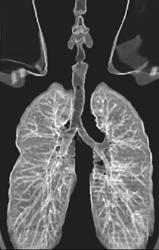

Lung Cancer With Adenopathy